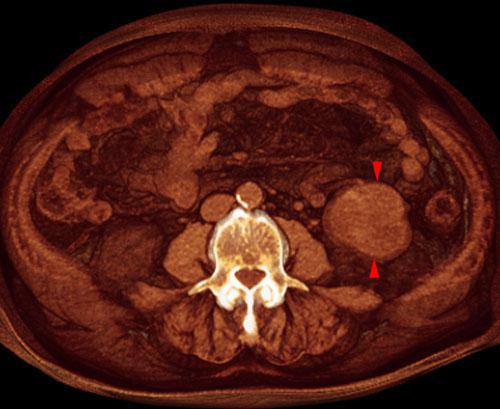

Quiste renal complejo sugestivo de neoplasia

VR seccional. Visión axial caudal. En exploración sin contraste se visualiza lesión nodular algo hiperdensa (puntas de flecha) en fosa renal izquierda